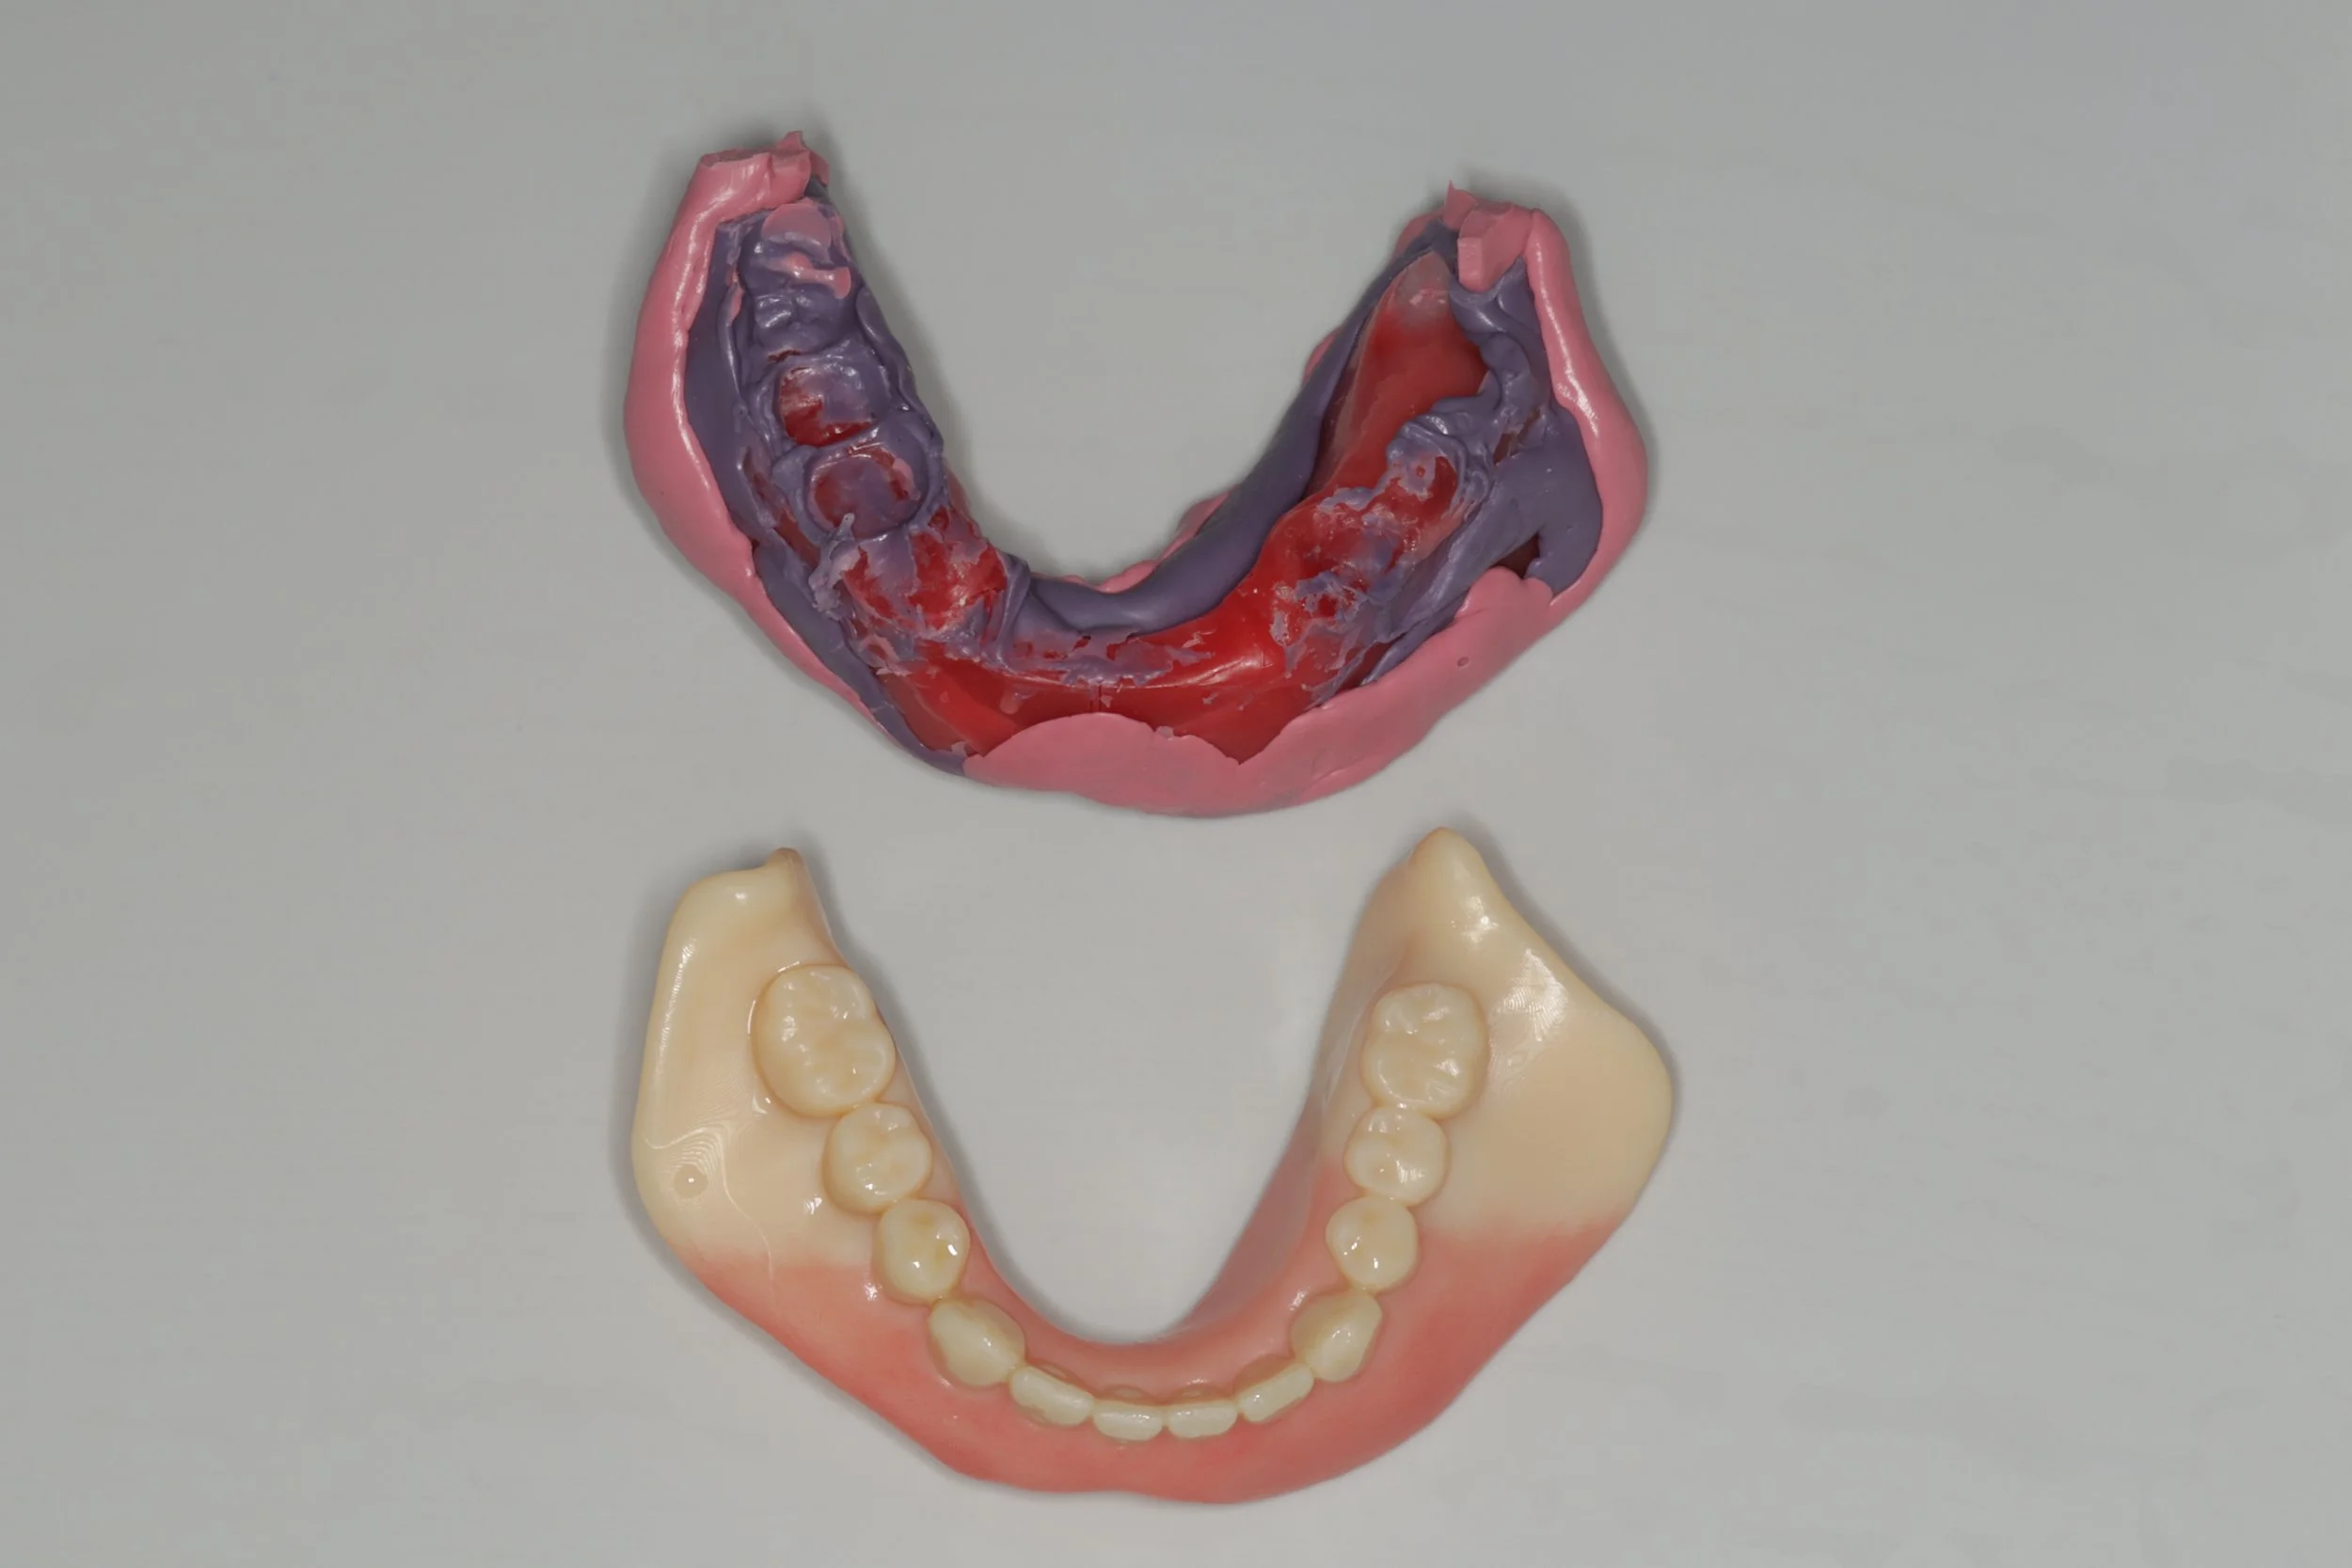

1回目

他院で入れ歯を作ったけど あまり使わなかったことで、前歯が折れてグラグラな状態でしたが、デジタルでの型取りにて、製作開始。

2回目

連結されている前歯を切断するとともに、折れた根の抜歯を行い、その後デジタルデンチャーを装着し機能回復を開始しました。

ポリフレックス

デジタルデンチャーの中でも、製作過程の多くをデジタル技術で製作。完全メタルフリーなので金属アレルギーの心配もありません。